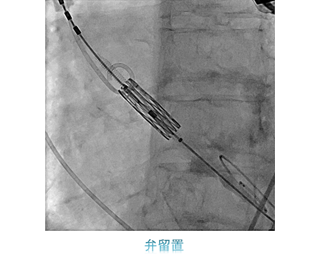

一方治療には、狭くなった冠動脈にステントを留置する冠動脈ステント留置術(PCI)をはじめ、心臓以外の動脈や静脈を拡張させる血管拡張術(PTA)、頻脈性不整脈の原因となる電気回路を遮断させるため、心筋に高周波電流を流して焼灼するアブレーションや、徐脈性不整脈に対するペースメーカー埋込術(PMI)、除細動器のデバイス埋め込み術(ICD)などがあります。